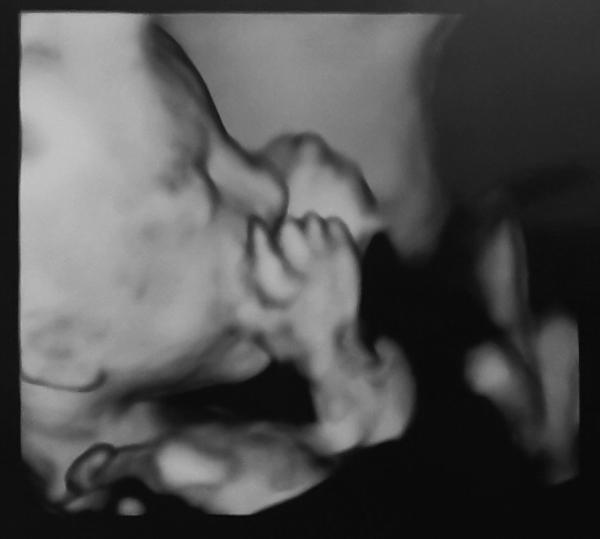

Wir hatten heute unseren Screeningtermin. Das Baby ist total aktiv und liegt in Querlage. Mit dem Gesicht so stark in die Plazenta gekuschelt, dass wir leider die Naern- und Lippenpartie nicht richtig sehen konnten, dementsprechend gibt es auch kein "Modelbild". Die Trikuspidalklappe konnte man leider aufgrund der Lage ebenfalls nicht richtig beurteilen, die war beim ETS noch undicht. Das wird in 4 Wochen nochmal geschaut.  Insgesamt war alles toll entwickelt! Und es war richtig schön so lange nach dem Baby schauen zu können.    Er ist auch wirklich ein Junge, ich bin total froh nun auch ein Bild gesehen zu haben und nicht nur den Nipt.   Meine Arterien zeigen Wiederstände mit Notching bzw angedeutetem Notching, für 21+0 SSW ist das aber im Rahmen.   Er wiegt ca 380 Gramm, im Moment habe ich bei mehrmaligem Testen eigentlich immer Spuren von Eiweiß, meistens + Eiweiß im Urin, aber der Blutdruck ist nach Absetzen von Cariban gesunken.    Ich drücke euch die Daumen für eure Ultraschalle   Liebe Grüße

Huhu 🙂 Ziemlich ruhig hier bei uns geworden... Es freut mich, dass dein 2. großes Screening insgesamt positiv war und die Klappe wird in 4 Wochen bestimmt auch dicht sein. 🍀 Und auch die Bilder sind schön geworden, auch wenn es kein richtiges Profilbild gab. Smiley nr152.gif Ich kann nachempfinden, dass es doch nochmal was anderes ist, wenn man das Geschlecht dann auch selber im Ultraschall erkennt. Das war bei uns auch so, erst dann kann man es "so richtig glauben". Seit wir die Ergebnisse aus dem NIPT wissen, wurde auch bei jedem Ultraschall nochmal gezeigt, dass es wirklich ein Mädchen ist. 😁 Wir hatten diese Woche die zweite Feindiagnostik. Es war so schön, der Ultraschall ging über eine halbe Stunde und wir konnten so viel von ihr sehen. 🩷 An sich ist im großen und ganzen alles in Ordnung, allerdings sind ein paar Sachen aufgefallen, die mich verunsichern. Zum einen ist sie bereits 620g schwer bei einer Größe von 28cm. Das ist deutlich zu viel für die Woche. Innerhalb von 3 Wochen hat sie damit ihr Gewicht verdoppelt obwohl sie "nur" 4cm gewachsen ist. Angeblich habe ich auch deutlich zu viel Fruchtwasser, was somit beides Indizien für Schwangerschaftsdiabetes sind. Den hatten wir ja aber eigentlich schon vor Wochen ausgeschlossen. Dann kommt dazu, dass ich so gerne per 3D einen genauen Blick auf ihre Nasen- und Lippenpartie bekommen hätte. Es wurde allerdings nur ein einziges Bild gemacht und da hatte sie ihre Hände genau davor. Es wurde lediglich in 2D nach der Lippe geschaut, dass da alles okay ist, aber für mich als Laie hat da leider das deutlich Visuelle als Bestätigung gefehlt.  Ansonsten ist aber wirklich alles positiv gewesen, alle Fingerchen dran usw. Ihre Füße haben 4,2cm gemessen, ihr Ohr 2,1cm und der Kopfumfang liegt schon bei 22cm. Das Herz sah top aus ebenso wie das Gehirn und die anderen Organe. Viele Werte waren wieder überdurchschnittlich, teilweise auf der 98. Perzentile und überwiegend der 25. Woche entsprechend. Nach dem Fruchtwasser habe ich dann später nochmal recherchiert, dass die Messwerte eigentlich vollkommen in der Norm waren/sind. Bin gespannt, was meine Gyn nächste Woche dazu sagen wird. Beunruhigt bin ich trotzdem, da unsere Wunsch-Klinik nicht bei SS-Diabetes entbinden kann und abgesehen davon, birgt zu viel Fruchtwasser ja auch Risiken. 🤔 Tritte merken wir nach wie vor deutlich auch von außen. Sie ist aktuell in BEL und das merke ich leider oft an meiner Blase - ihre Füße liegen genau darüber. 🫣 Ich hoffe, es geht allen gut. Lasst mal wieder was von euch hören. Liebe Grüße Susuba, 22+1